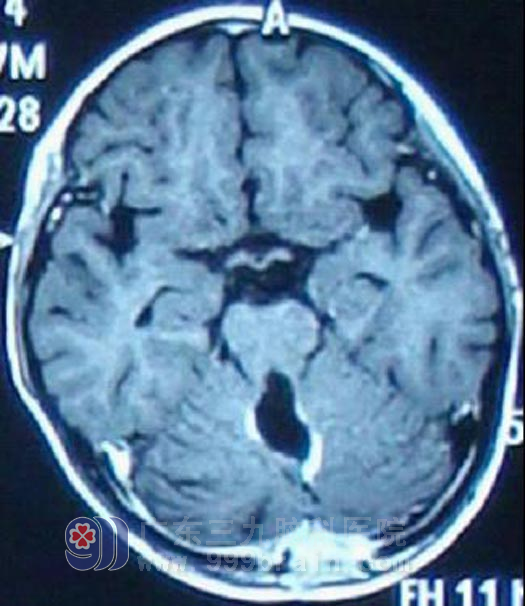

7岁的扬扬是一个快乐的小女孩,今年3月开始无诱因出现恶心呕吐情况,开始约每天一次,呈喷射状,开始父母未引起重视,以为只是普通的感冒,未进行积极地治疗,渐渐呕吐频繁加重,4月到当地儿童医院就诊,诊断为地中海贫血,予对症治疗后呕吐症状无好转。即至广州某肿瘤医院就诊,头颅MR显示为小脑蚓部囊性病变,专家考虑为毛细胞型星形细胞瘤,不排除髓母细胞瘤。经过完善相关检查后5月24日行占位切除术,术后病理显示为髓母细胞瘤。手术后扬扬恶性呕吐症状消失,出现行走步态欠稳。在家康复一段时间后,6月24日我院就诊,扬扬一般情况良好,经过详细计划后即开始行全中枢放疗,放疗后复查头颅MR示术区边缘强化明显减退,再行术区适形加量放疗。http://www.999brain.com/

放疗后